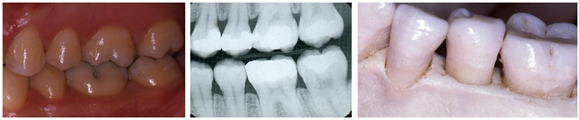

You can easily see your gums and teeth in a mirror. Your gums should be lie flat and feel fairly firm to the touch, and unless the teeth themselves are spaced apart, they come to a point between the teeth so you you not see any open space. If your gums look red, swollen, or bleed when you brush you likely have the mildest form of periodontal (gum)disease called gingivitis. This is caused by certain bacteria in your mouth that form a sticky substance called plaque that clings to your teeth and forms a home for the bacteria, which produces toxins that irritate and inflame the gums. At this point the condition is fairly easy to reverse with good home care and some routine professional care.

Hidden from view is your jaw bone that surrounds and supports the teeth and gums. When you lose the bone from around teeth, they become loose and the gums recede. Bone loss usually occurs when gingivitis is not cared for and it progresses to periodontitis. With periodontitis the gums can separate from the teeth and form pockets or spaces down the sides of the teeth that are difficult if not impossible to take care of with only home care. Eventually the toxins reach and destroy the bone supporting the teeth and when enough bone is lost the tooth becomes loose and may need to be removed. There may not be early symptoms of periodontitis which is why it is important to get regular dental check-ups even if you are not feeling pain or experiencing problems.

Besides checking your gums with a slim instrument called a periodontal probe, the dentist uses x-rays to see the bone around the teeth to determine if bone loss has occurred. While x-rays are quite valuable, a dentist’s complete examination and experience are required to interpret them to determine an accurate diagnosis. Once periodontitis develops regular and routine periodontal maintenance care is vital to maintain long-term health of your gums.